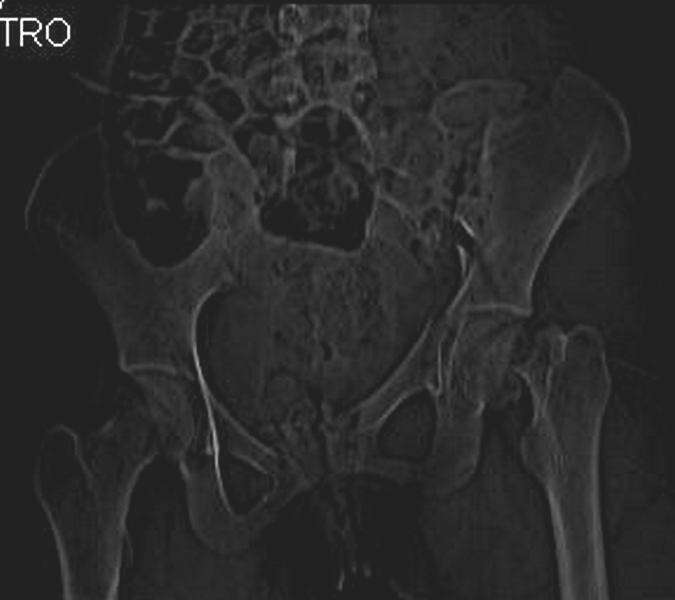

Уважаемые коллеги! С прошедшеми Вас праздниками. Теперь ближе к трудовым будням. Поступила 16 летняя девушка неделю назад. Механизм травмы падение с 5 этажа. Краткий диагноз:закрытый перелом левой ключицы, левого плеча, закрытый вертикально и ротационно нестабильный перелом костей таза:закрытый перелом левой подвздошной кости, переломы лонной кости справа, перелом обоих колонн вертлужной впадины слева;субкапитальный перелом шейки левой бедренной кости со смещением. По тактике лечения таза возникли следующие вопросы: 1. С чего начать - фиксации переломов вертлужной впадины или устранения деформаций таза? 2. Надо ли фиксировать шейку или фиксировать бедро в аппарате вместе с тазом, а после сращения таза планировать ТЭП ТБС? Если имеются еще какие подводные камни, будем рады выслушать.Спасибо.

На снимке ацетабулума редко встречающийся очень низкий перелом, наверное, трудно было репозицию через один доступ? Перелом как бы замкнулся в квадрилатеральной поврехности.

Ничего такого особенного в переломе вертлужной впадины не опознал. Транстектальный перелом хорошо репонируется щипцами, установленными через седалищную вырезку.

В положении на спине подвздошным и надлобковым доступом восстанавливается тазовое кольцо, фиксация пластинами. При хорошей репозиции может улучшиться конгруэнтность в суставе.

Затем, если положение хорошее, закрытый остеосинтез шейки винтами.

Если нет - в положении на боку, синтез задней колонны из наружно-латерального доступа и синтез головки винтами, но уже под визуальным контролем.